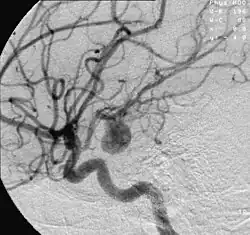

![]() | |

| Angiography of an aneurysm in a brain artery. The aneurysm is the large bulge in the center of the image. | |

An aneurysm is an outward bulging, likened to a bubble or balloon, caused by a localized, abnormal, weak spot on a blood vessel wall.[1] Aneurysms may be a result of a hereditary condition or an acquired disease. Aneurysms can also be a nidus (starting point) for clot formation (thrombosis) and embolization. As an aneurysm increases in size, the risk of rupture increases, which could lead to uncontrolled bleeding.[2] Although they may occur in any blood vessel, particularly lethal examples include aneurysms of the circle of Willis in the brain, aortic aneurysms affecting the thoracic aorta, and abdominal aortic aneurysms. Aneurysms can arise in the heart itself following a heart attack, including both ventricular and atrial septal aneurysms. There are congenital atrial septal aneurysms, a rare heart defect.